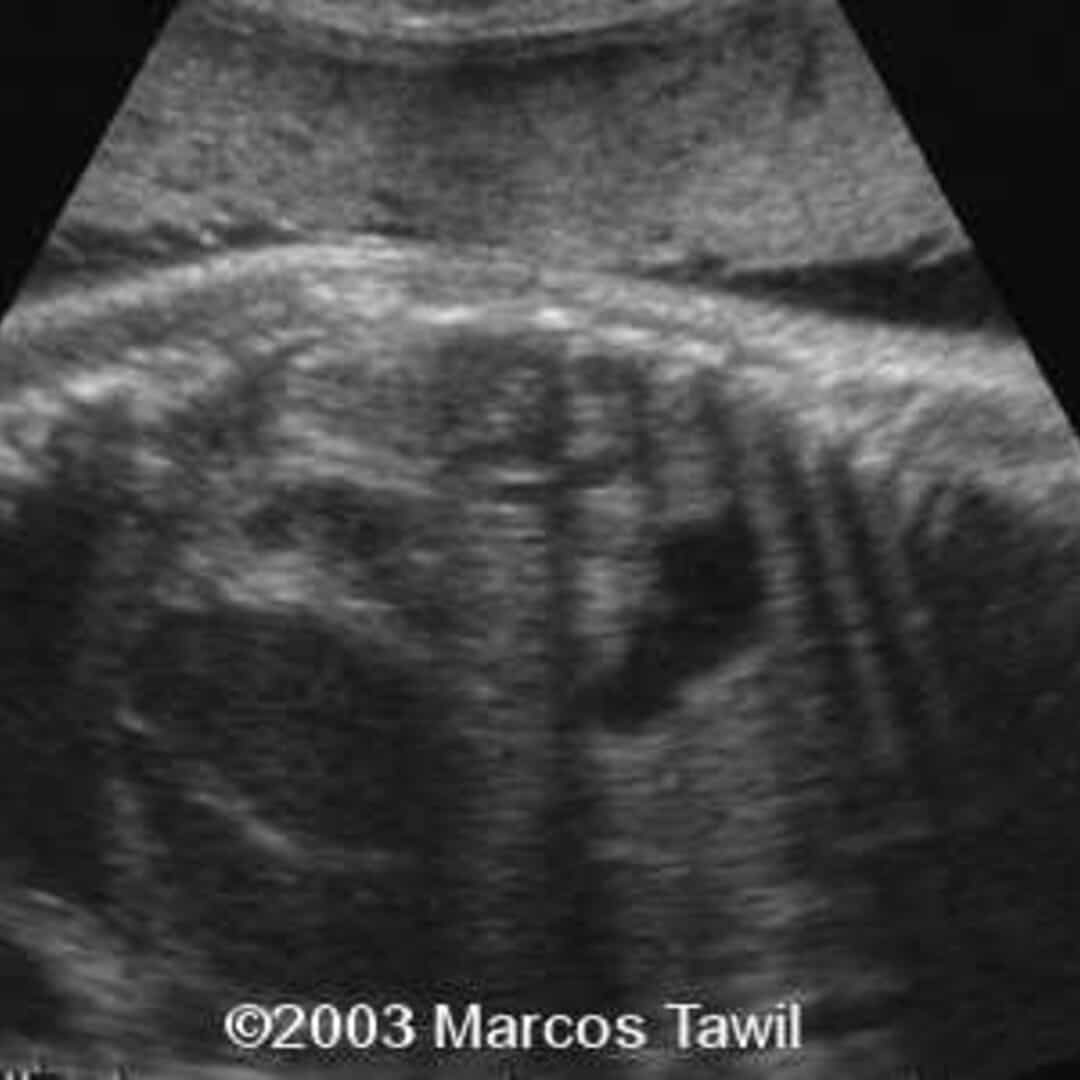

Figure 1 from Three Cases of Meconium Plug Syndrome. Semantic Scholar

Figure 1 from Three Cases of Meconium Plug Syndrome. Semantic Scholar Plug Syndrome Definition Meconium plug syndrome is a relatively common cause of transient functional colon obstruction in newborn, characterized by. Meconium plug syndrome is most often a benign cause of obstruction that clears after rectal stimulation or administration of contrast enema;. Meconium plug syndrome is colonic obstruction caused by thick meconium. Diagnosis is based on radiographic contrast enema and. Meconium plug syndrome is. Plug Syndrome Definition.